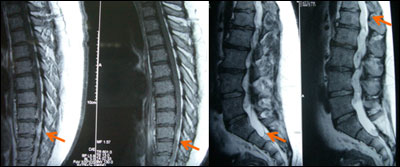

术前图片:T9-10背侧髓外硬膜下占位,有强化,T12-S1占位,轻微强化。